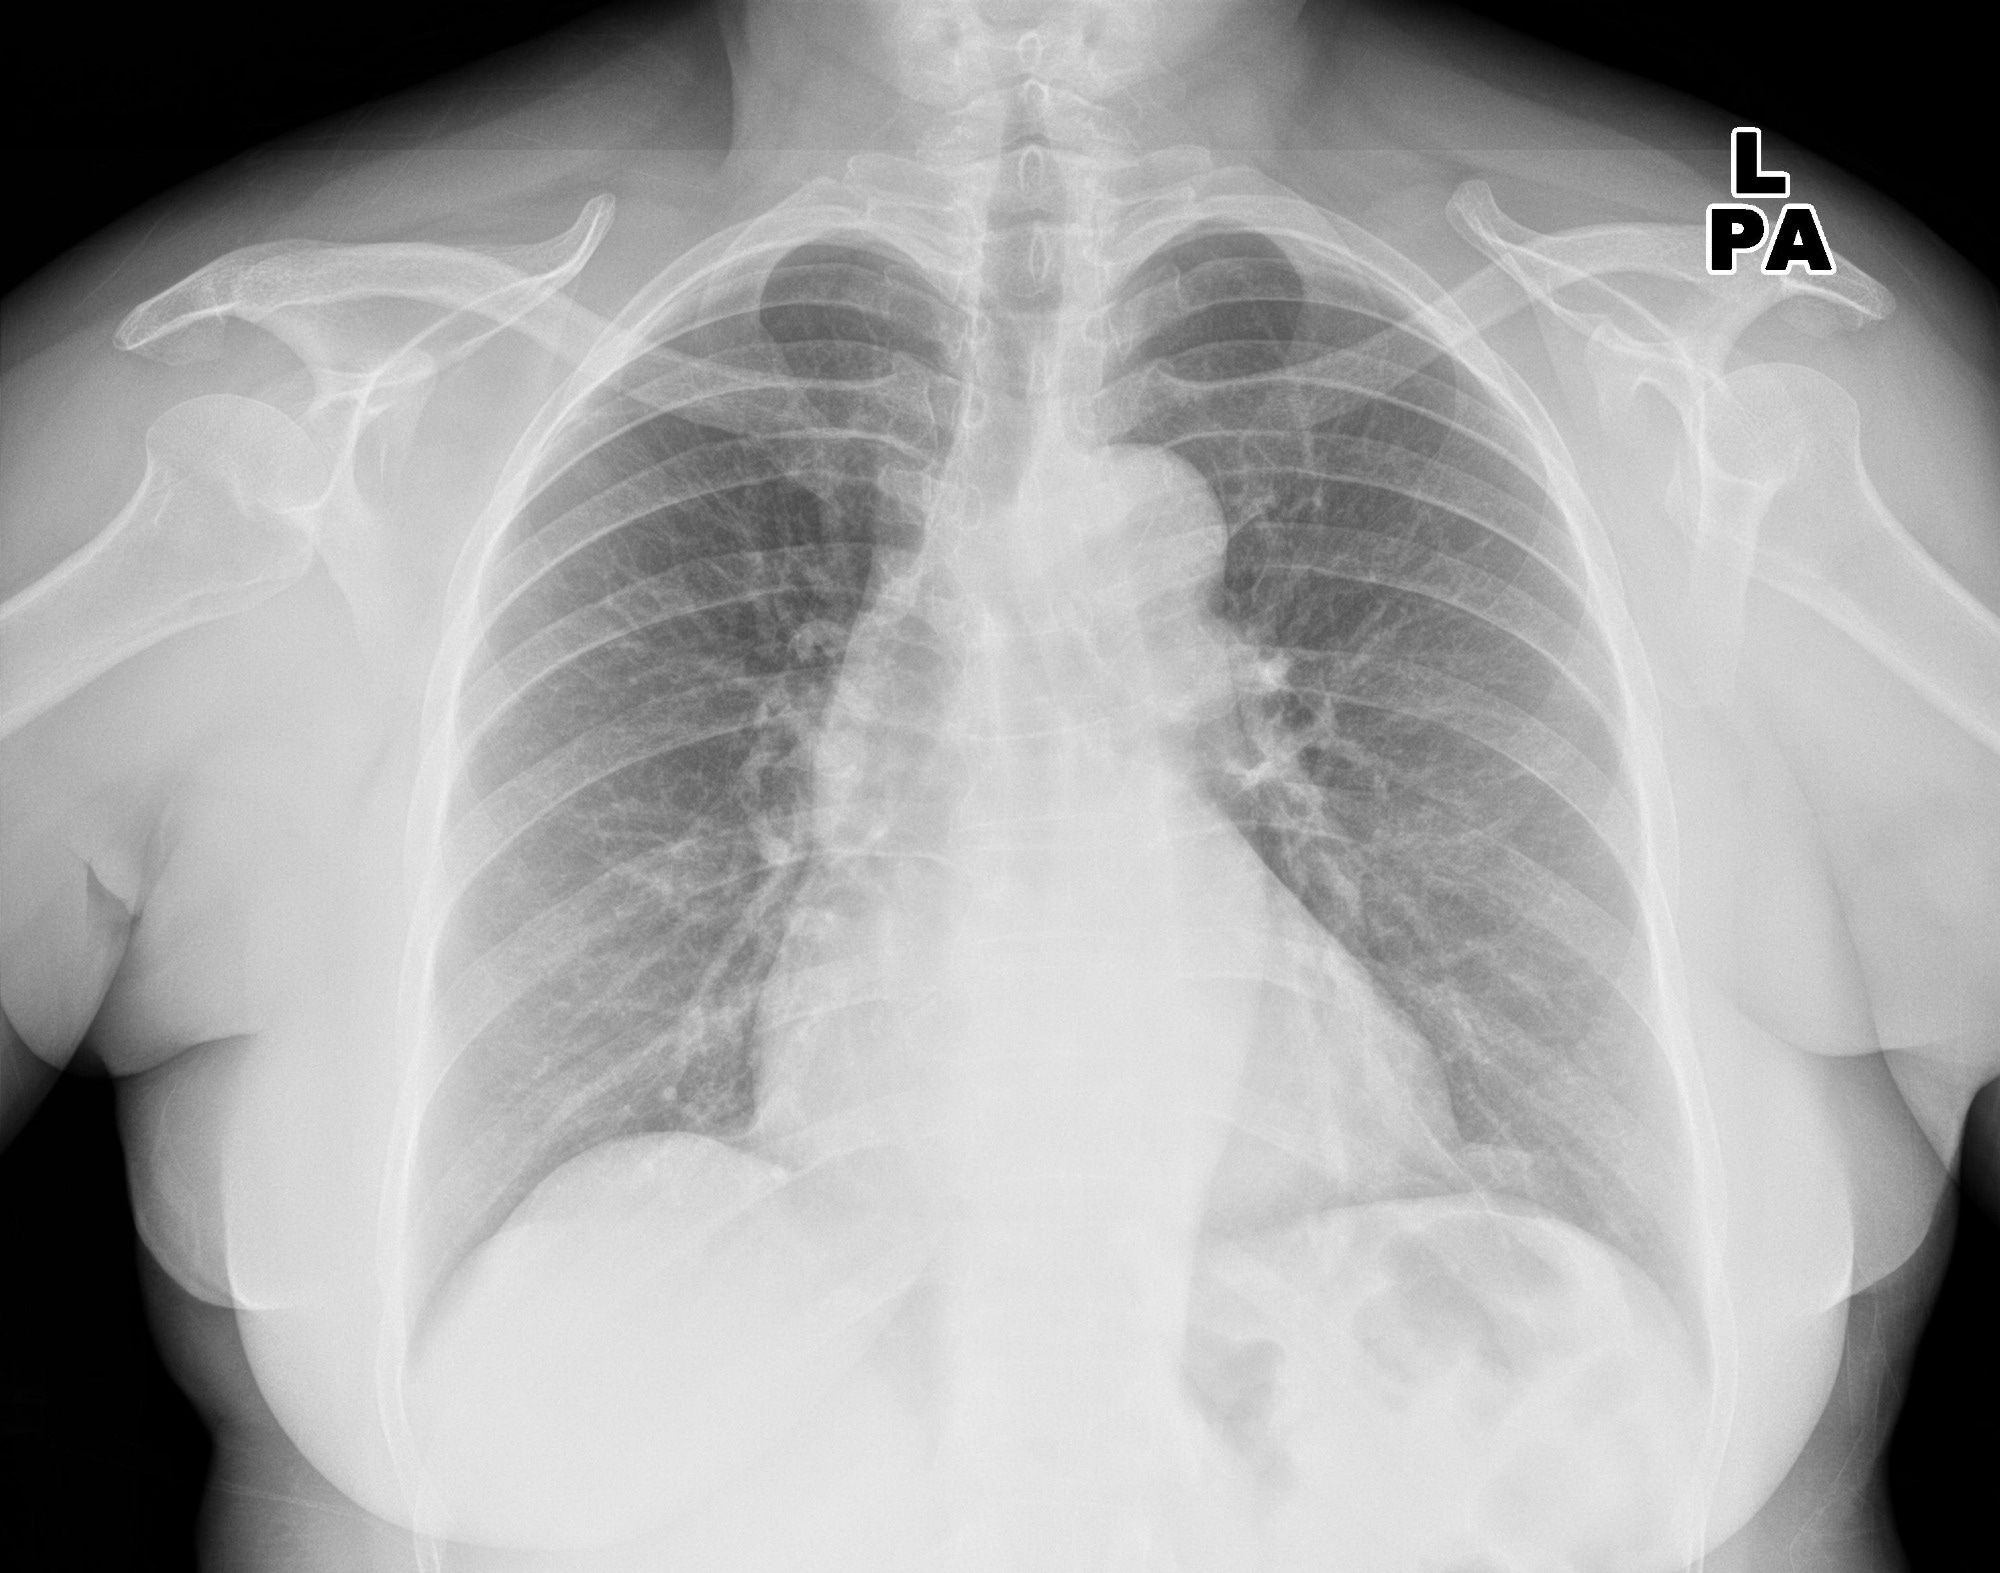

In a recent study published in the journal Radiology, researchers evaluated the diagnostic accuracy of four artificial intelligence (AI) tools in detecting pleural effusion, airspace disease, and pneumothorax on chest radiographs.

Study: Commercially Available Chest Radiograph AI Tools for Detecting Airspace Disease, Pneumothorax, and Pleural Effusion. Image Credit: KELECHI5050 / ShutterstockStudy: Commercially Available Chest Radiograph AI Tools for Detecting Airspace Disease, Pneumothorax, and Pleural Effusion. Image Credit: KELECHI5050 / Shutterstock